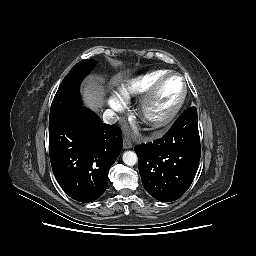

Reconstructed NATIVE CT scan (cycle consistency)

No window - Raw intensity values

Lung window (WL -600, WW 1500 β†’ Low βˆ’1350, High +150)

Mediastinum window (WL 40, WW 400 β†’ Low βˆ’160, High +240)